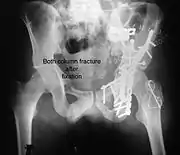

Posterior wall fracture fixed with screws and plate